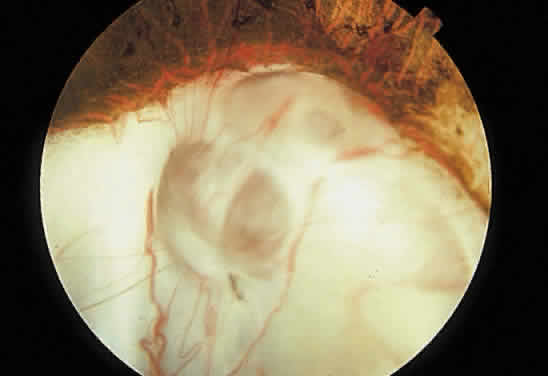

Retinochoroidal colobomas are glistening white or yellow defects with distinct borders that occur inferior or inferonasal to the optic disc (Fig. 12). They may extend up to and involve the optic disc (Fig. 13), or they may be seen as isolated chorioretinal defects. The margins of the coloboma often are pigmented, and the defect is filled with abnormal retinal tissue. Anteriorly, the defect can extend as far as the iris and produce an inferonasal gap (Fig. 14). These anomalies may occur in otherwise normal persons or in association with chromosomal abnormalities or multisystem diseases, such as trisomy 13, the Aicardi syndrome, Goldenhar's syndrome, and the CHARGE association.148,152,153 Occasionally, autosomal dominant or recessive inheritance patterns are found, but often none are evident.152 In families with autosomal dominant inheritance, variable expression of the genetic trait makes genetic counseling difficult.154

Fig. 12. Isolated retinochoroidal coloboma with pigmented borders positioned inferior to the nerve head. The sclera is visible through the thinned, overlying retinal tissue.

Embryologically, retinochoroidal colobomas arise from failure of the embryonic fissure to close. Consequently, the inner and outer layers of the optic cup are abnormal in this region. The inner layer (sensory retina) usually is present as a membrane of undifferentiated retina that may have blood vessels going through it (see Figs. 12 and 13). The outer layer (RPE) is absent, and since the choroid is dependent on the RPE for its development, it also is lacking.